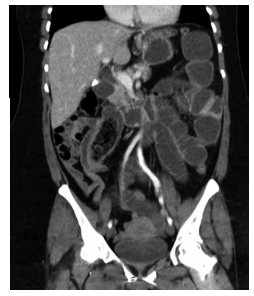

Iniciou episódios recorrentes de dor abdominal em andar

superior, náuseas e vômitos pós-prandiais há 2 semanas, com piora importante nas últimas 24 horas, quando

buscou o pronto-socorro. Ao exame físico, apresenta dor

em andar superior do abdome, sem sinais de peritonite.

Realizou a tomografia computadorizada demonstrada na

imagem a seguir: